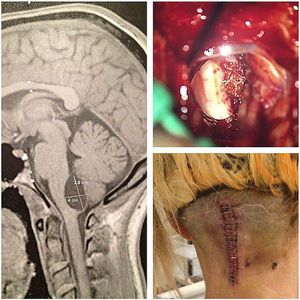

This incredible personal case from last January was sent to me by @hollatojenny , which had a cyst attached to her lower part of the Brain Stem between the cerebellum and medulla oblongata (above her spinal cord). She had underwent emergency brain surgery while knowing that the outcome might be complicated with memory loss and no motor skills for around a year. She was undertaken for emergency suboccipital craniectomy, the cyst expanded when the surgeon lifted the cerebellum and popped out the back of the cyst dragging the cord with it. Drainage of the cyst was done, and the cord returned back to its place. Surprisingly enough, postoperatively, she woke up with memory and motor skills, as well as normal vital signs, the room bursted into tear. She's doing well ever since. π